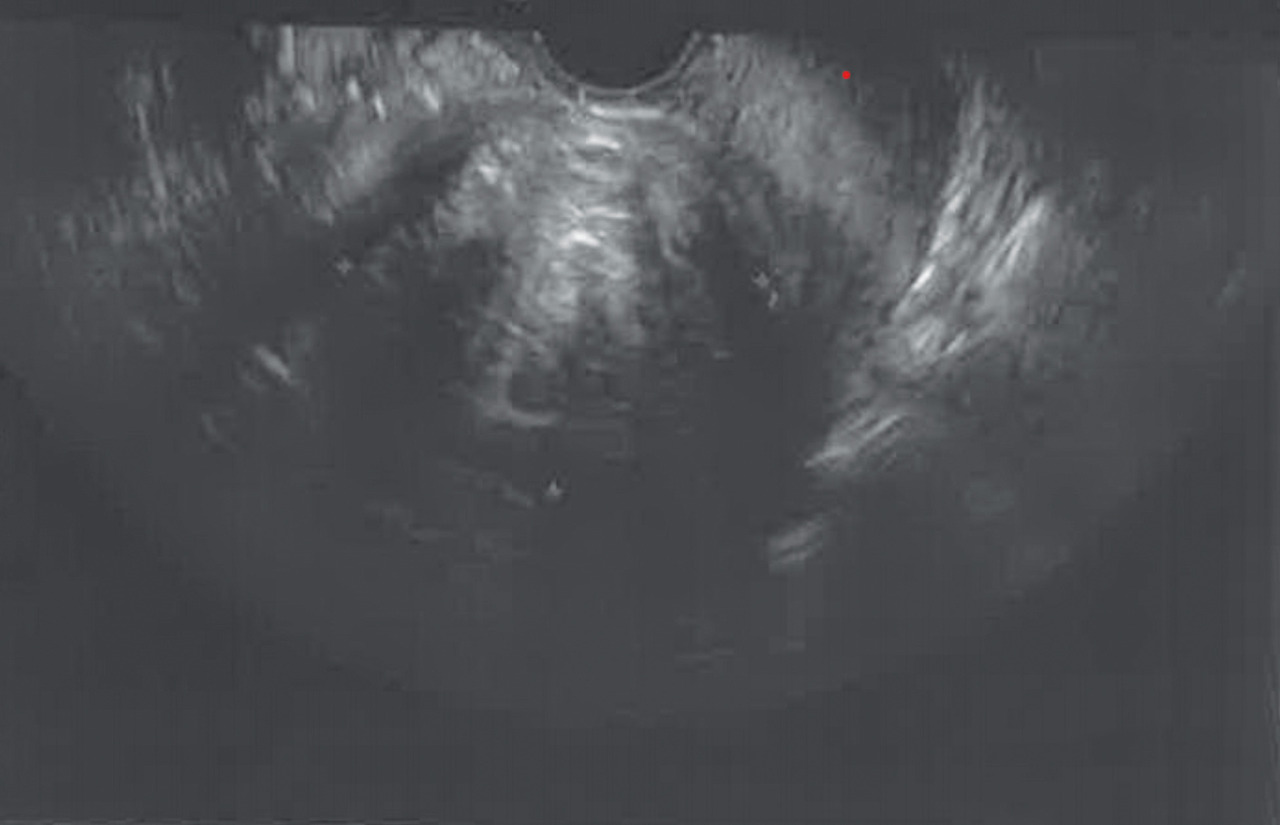

Hystéroscopie diagnostique

Elle consiste à introduire dans la cavité utérine un endoscope (fig. 3), qui peut être souple ou rigide. La distension de la cavité utérine se réalise au sérum physiologique ou à l’aide de CO2. Cet examen diagnostique peut se réaliser en consultation, sous anesthésie locale et, du fait du faible calibre des hystéroscopes, ne nécessite en général pas de dilatation du col utérin. Elle peut également être réalisée sous anesthésie générale, elle est alors associée au curetage biopsique ou hémostatique.

La visualisation de la cavité permet de faire le diag­nostic de polype, de fibrome sous-muqueux, d’hyperplasie endométriale ou de cancer de l’endomètre.

L’hystéroscopie est en général accompagnée de biopsies endométriales.